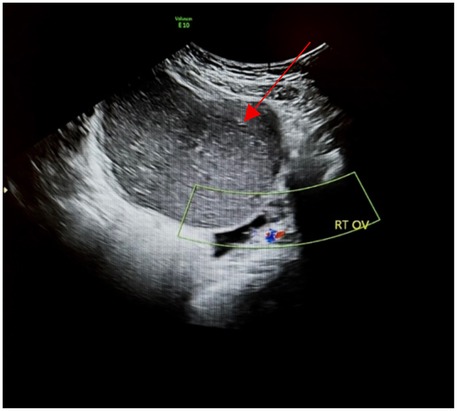

Pelvic ultrasound identified a large, well-defined, predominantly cystic mass arising from the right ovary, with internal septations and echogenic components suggestive of fat content (Figure 1). MRI of the pelvis confirmed a complex multilocular cystic lesion, measuring approximately 8–9 cm (Figure 2). No solid enhancing nodules or invasive features were seen. There was no evidence of pelvic lymphadenopathy or bone marrow infiltration.

Figure 2. Sagittal T2 fat suppressed weighted images shows 9 × 8 cm well defined homogeneous intermediate T2 signal intensity right adnexal cystic mass (red arrow).